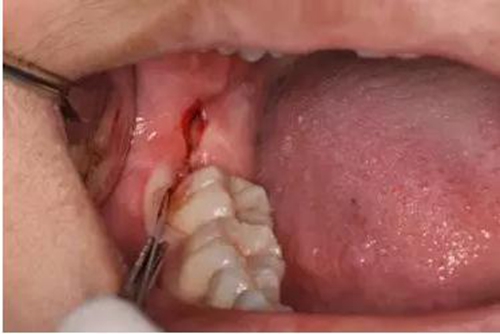

圖12. 近中、頰側(cè)兩個(gè)部位用挺使48牙冠完全脫位

圖13.清理牙槽窩、對位傷口

圖14.僅在遠(yuǎn)中縫合兩針,不宜太緊。